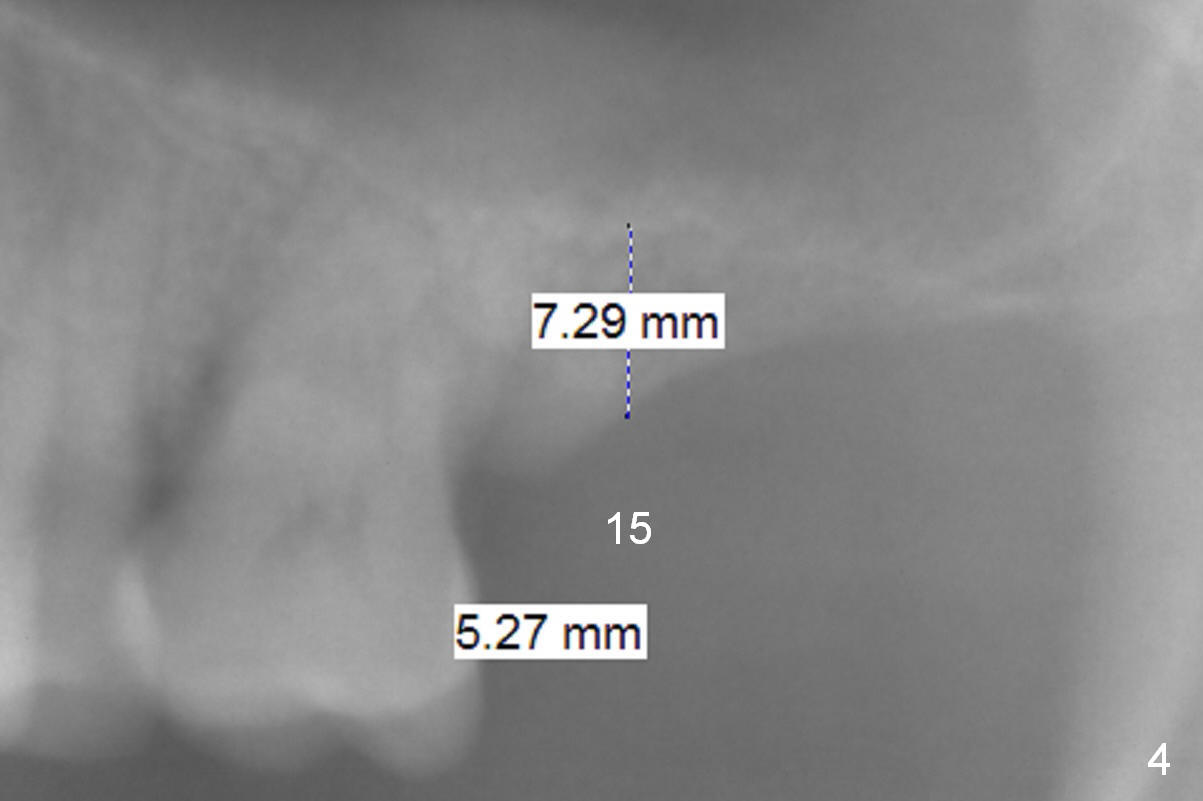

A 54-year-old man has crowded dentition with moderate to advanced periodontitis (Fig.1) and bruxism (exostosis (Fig.6 *)). It is essential to re-establish complete dentition by placing implants at #6, 7 and 15 initially and more when other teeth are lost. The ridge at #6 and 7 is moderately atrophic (Fig.7), while that at #15 severely atrophic (Fig.8). Due to narrow mesiodistal space at #6 and 7 (Fig.2), narrow and 1-piece implants may have to be placed (Fig.3).